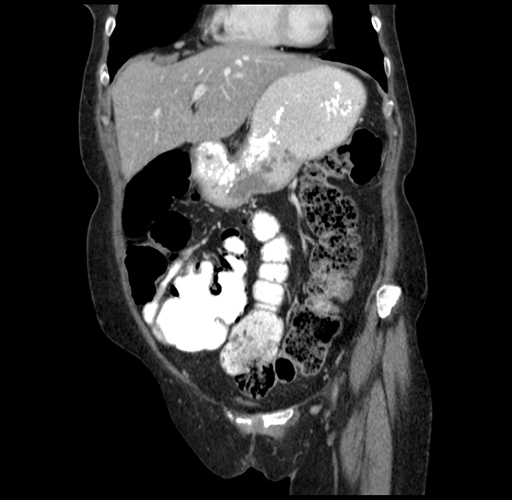

Axial Venous

Coronal Venous

Imaging analysis

Based on your CT findings, which issue(s) would give reason for "planned slowing down moment(s)" in this case?

Considering a standard right hepatectomy procedure, what step(s) of the operation would you do differently in this case?